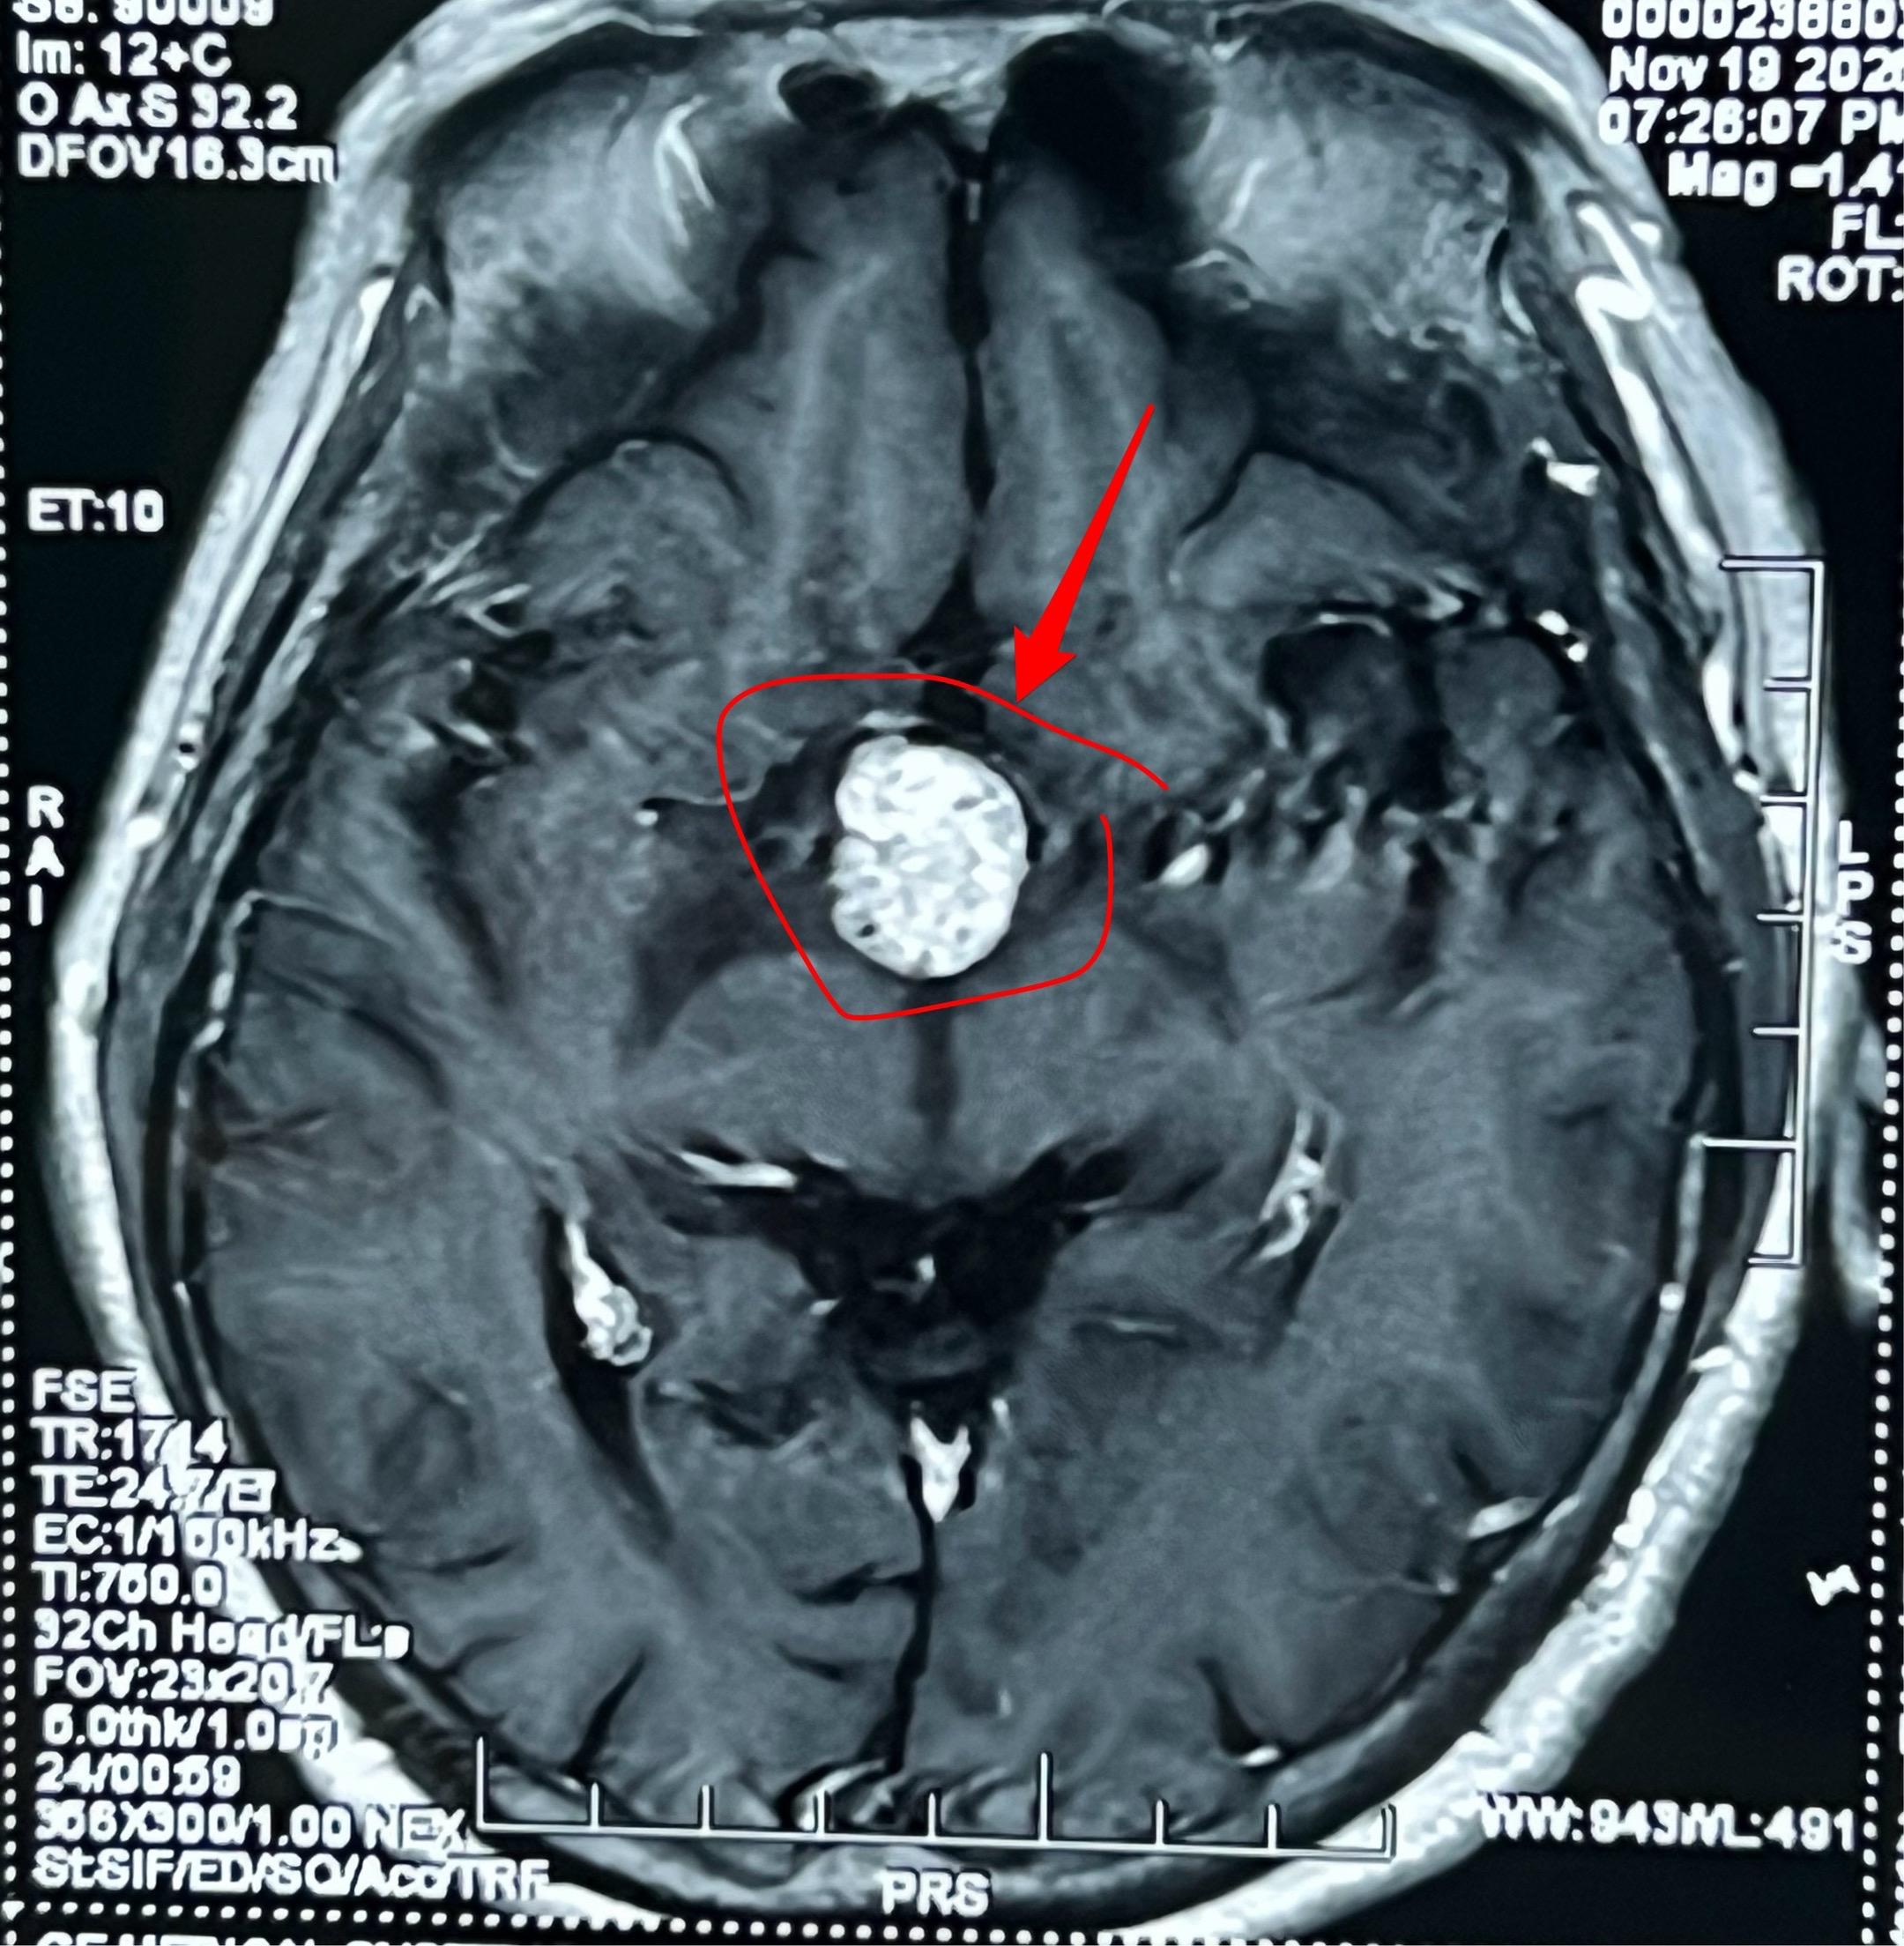

颅咽管瘤可以在任何年龄发病。72岁老人也患颅咽管瘤! 很多人都认为颅咽管瘤是小孩子得的病,其实不然。 70岁以上的老人也会患上颅咽管瘤这种病。这个72岁的青海省女性,因为视力下降、头痛到医院检查,发现了这个颅咽管瘤。 12月5日在我科行开颅手术将肿瘤完全切除。(今年我科的第193个颅咽管瘤手术。